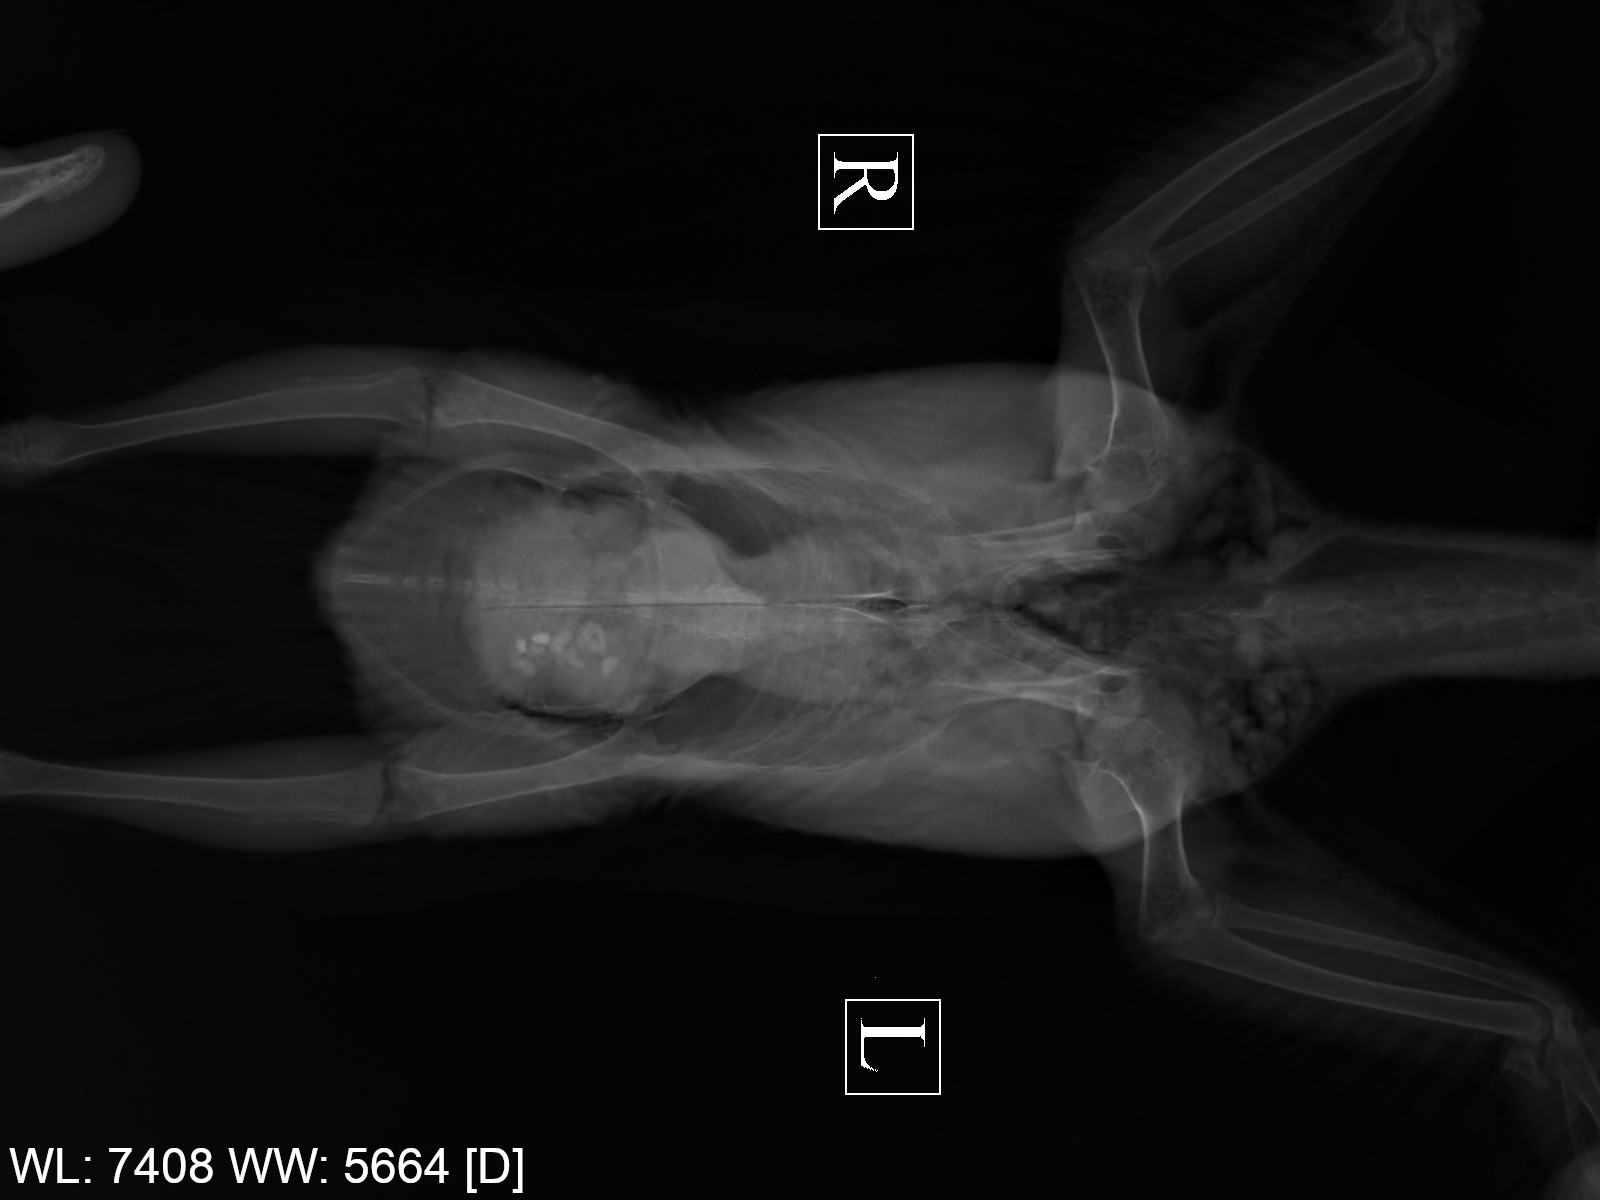

напомните пожалуйста рентген лёгких в двух проекциях не делали?

Да, рентген был в октябре, уже выкладывал. Ни от паразитов, ни глистогонку не делал.

@ната1805, ну, Рыжему уже 3 раза делали рентген, я всё тут выкладывал... Zosia смотрела, но ничего конкретного не сказала про лёгкие и воздушные мешки. Правда, чёткость рентгена не очень, но лучше в моей глуши, к сожалению, не сделать – не тот уровень оснащения.

@ната1805 Плохо. Повторный рентген – уже после курса антибиотикотерапии – очень плох:

.thumb.png.b862e04782aadef0209ef50f109bb175.png-.thumb.png.6edb55837bbb4c3f98b19626d986f64f.png

Разительные изменения, по сравнению с октябрьскими снимками: Zosia констатировала злокачественную опухоль правой почки, проблемы с сердцем (в т.ч. расширена левая дуга аорты), множественные гранулёмы в лёгких и новообразование в слизистой зоба. Всего этого не было на октябрьском и более ранних снимках. Может ли патологическое изменение почки на снимке быть не опухолью, а инфекционным воспалением – Zosia отвечать не стала. Видимо, не может.